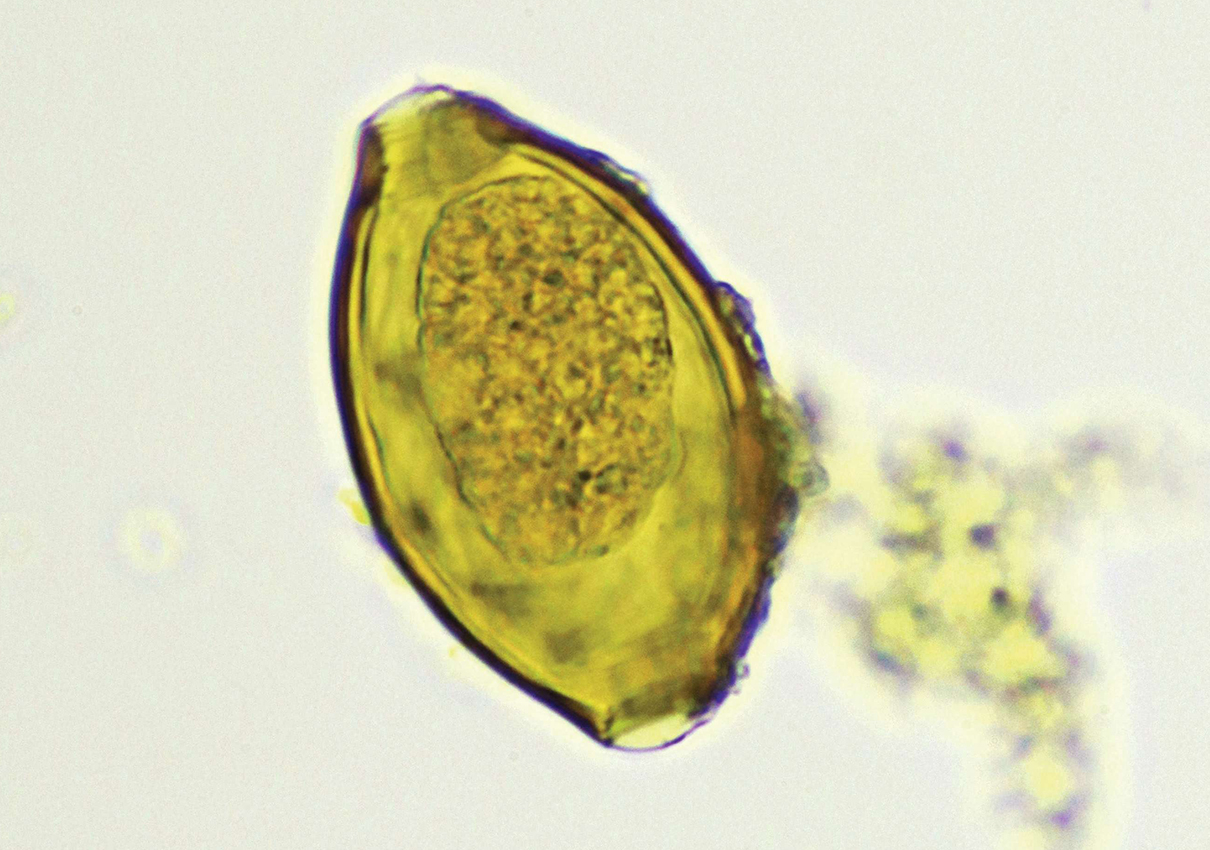

Big Viking Poo . The huge poo measures in at a massive 20cm (8 inches) long and 5cm (2 inches) wide and was discovered by archaeologists from york archaeological trust whilst excavating the viking settlement of jorvik (york)! Fossilized human feces dug up from a viking site in york, england. Measuring 20 centimeters (8 inches) long and 5 centimeters (2 inches) wide, the massive coprolite is believed to be the largest example of fossilized human poop (paleofeces) ever found. Discover lloyds bank coprolite in york, england: Fossilized human feces dug up from a viking site in york, england. It contains large amounts of meat, pollen grains, cereal bran, and many eggs of whipworm and. An enormous viking poo may the longest human faeces ever recorded.

Measuring 20 centimeters (8 inches) long and 5 centimeters (2 inches) wide, the massive coprolite is believed to be the largest example of fossilized human poop (paleofeces) ever found. The huge poo measures in at a massive 20cm (8 inches) long and 5cm (2 inches) wide and was discovered by archaeologists from york archaeological trust whilst excavating the viking settlement of jorvik (york)! Fossilized human feces dug up from a viking site in york, england. Discover lloyds bank coprolite in york, england: Fossilized human feces dug up from a viking site in york, england. It contains large amounts of meat, pollen grains, cereal bran, and many eggs of whipworm and. An enormous viking poo may the longest human faeces ever recorded.